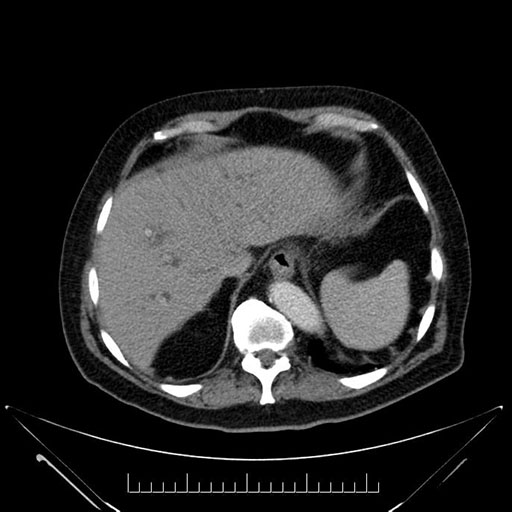

Axial - stented